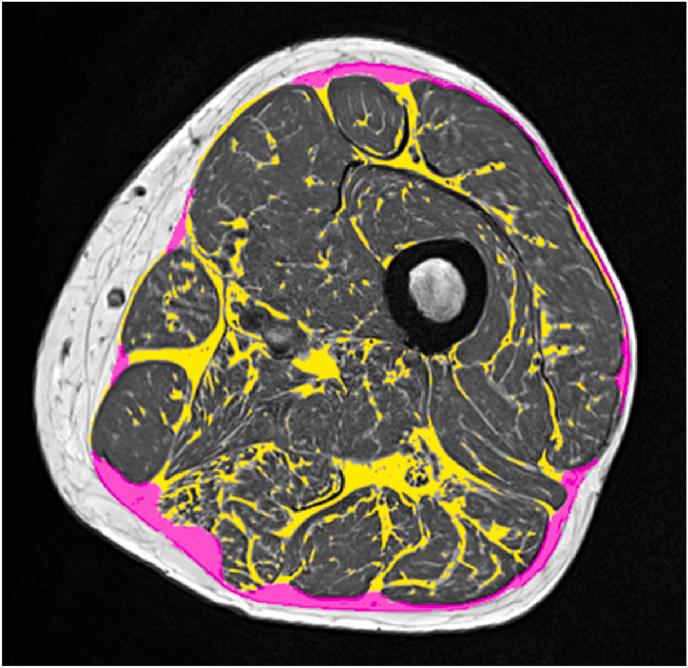

Magnetic resonance imaging (MRI) is the dominant 3D imaging modality to quantify muscle properties in skeletal muscle disorders, in inherited and acquired muscle diseases, and in sarcopenia, in cachexia and frailty.

MRI technology provides a rich toolset to assess muscle deterioration. In addition to classical measures such as muscle atrophy using T1 weighted imaging and fat infiltration using Dixon sequences, parameters characterizing inflammation from T2 maps, tissue sodium using non-proton MRI techniques or concentration or fiber architecture using diffusion tensor imaging may be useful for an even earlier diagnosis of the impairment of muscle quality.

磁共振成像(MRI)是用于量化骨骼肌疾病、遗传性和获得性肌肉疾病、肌肉减少症、恶病质和虚弱症中肌肉特性的主要三维成像方式。

MRI技术提供了一套丰富的工具来评估肌肉退化。除了使用T1加权成像测量肌肉萎缩和使用狄克逊序列测量脂肪浸润等经典方法外,通过T2 mapping表征炎症的参数、使用非质子MRI技术测量组织钠含量或使用扩散张量成像测量浓度或纤维结构,可能有助于更早诊断肌肉质量受损情况。